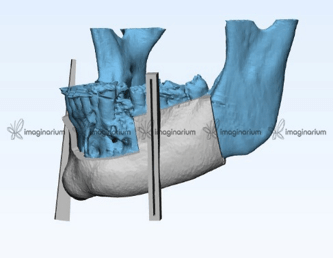

Working a case from the digital stand point begins with a CT – scan of the mandible with the pathology and a CT-angiography for the fibula. A CT- angiography is done to check for the patency of the peroneal artery to be harvested along with the graft. These files are provided in DICOM formats.

After the scan various softwares for eg.- Geoform , MAGICS etc are used to convert the DICOM file into .stl format which is essential for the virtual planning of the case.

The files are then uploaded onto the software; the various tools are then used to analyse the extent of the lesion and create a treatment plan. The accessed pathology is virtually resected by keeping safety margins11.

Simultaneously the fibula is analysed for the area to be resected depending on the anatomical considerations. Those include using the middle portion of the bone, not including the distal end of the bone to maintain its vascularity.

Cases which include the resection of the anterior section of the mandible are more difficult to rehabilitate as it entails reconstruction of the anatomical curvature. This can be achieved via virtual planning.

The cutting planes for the fibula are decided on the basis of the amount of graft needed for the reconstruction

The angles between these cutting planes act as a guide to achieve the anterior curvature of the mandible. Along with the angles the resected pieces help us gauge the height, width and placement of the implants

Post the planning two more stents are designed, one for the resection of the fibula and another for the implant placement

A 3D printed model of the mandible can also be printed to precontour the reconstruction plate12.

On the day of the surgery two surgical teams simultaneously resect the mandible and harvest the fibular graft using the previously printed stents, attach the reconstruction plate to the harvested fibular graft and then attach it to the remnant mandible; implants are placed there after using the stent. Following the implant placement there is a waiting period of 3-6 months for the graft to get accepted and implants to osseointegrate simultaneously.A prosthesis is then fabricated.